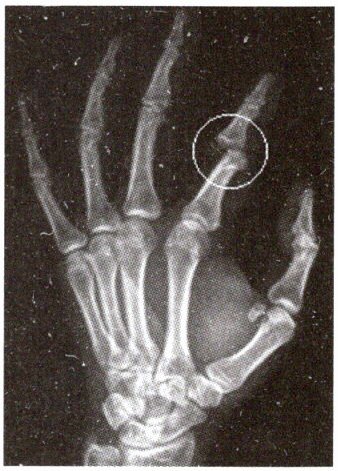

10. 某同学接快速飞过来的篮球时不得要领,造成手受伤。下图是他受伤部位的X光片,他手部骨头可能发生了(

A.骨折

B.关节脱位

C.骨裂

D.骨质增生

B